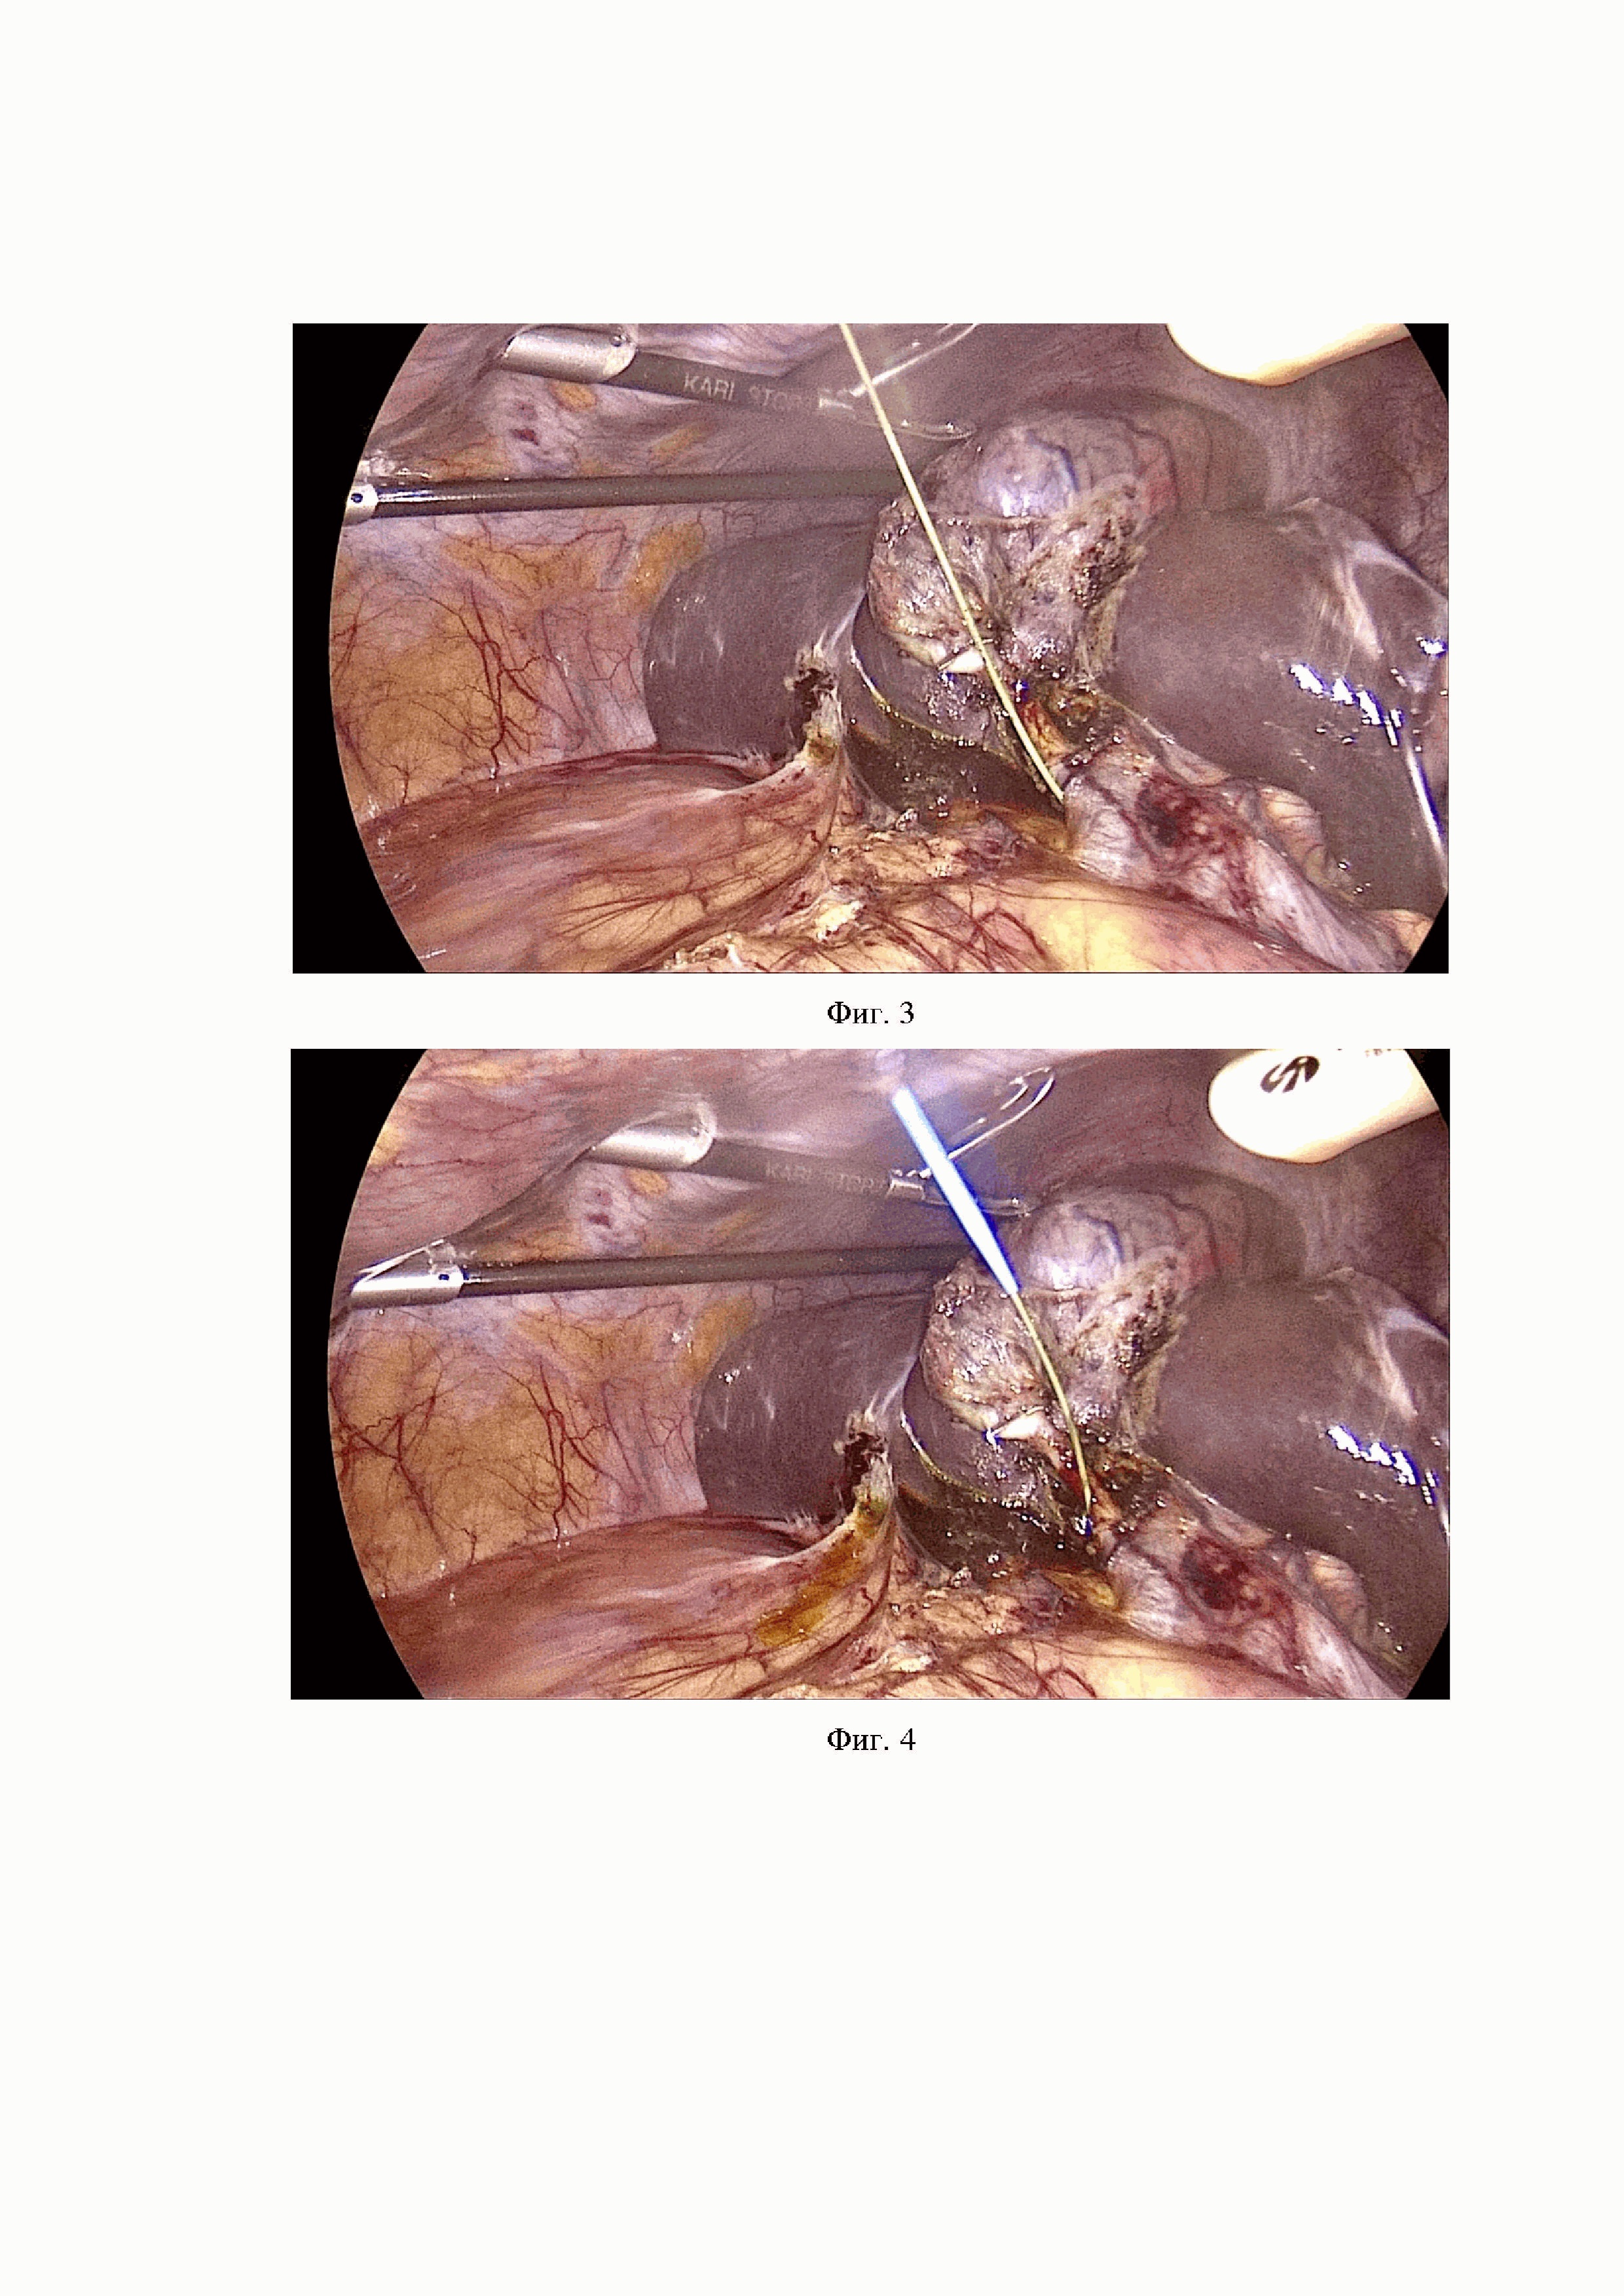

Фиг. 3 В брюшную полость через контрапертуру в правом подреберье введён тефлоновый проводник 0.035 inch. Для удобства установки и позиционирования тефлонового проводника осуществляется тракция за желчный пузырь, тефлоновый проводник через надсеченную культю пузырного протока устанавливается в ОЖП по направлению к ДПК на глубину, достаточную для его визуализации при эндоскопическом этапе операции или до появления чувства сопротивления продвижения проводника.

Фиг. 4 Бужирование передней брюшной стенки в области правого подреберья на тефлоновом проводнике.

По жизненным показаниям выполнена лапароскопическая холецистэктомия, при которой выявлен гангренозный калькулезный холецистит в рыхлом инфильтрате (Фиг.17). Произведено клипирование пузырного протока (Фиг. 18) и артерии, артерия пересечена, желчный пузырь отсепарован от ложа по методике «от шейки», пузырный проток надсечен наполовину. Подготовлен дренаж Холстеда-Пиковского со сформированным на проксимальном его конце дополнительным отверстием. Тефлоновый проводник введен в дистальную часть ОЖП через культю пузырного протока до появления чувства сопротивления дальнейшему прохождению, т.е установлен над зоной БДС. На тефлоновом проводнике выполнено введение дренажа Холстеда-Пиковского. (Фиг.19). Фиксация дренажа также выполнена эндоклипсой и лигатурой к пузырному протоку и лигатурой к коже. При фистулографии выявлен единичный конкремент в дистальном отделе общего желчного протока (Фиг.20). Послеоперационный период гладкий, пациент выписан на 7-е сутки послеоперационного периода.

На Фиг. 17 – 22 представлен вариант двухэтапного хирургического лечения пациента с деструктивным калькулезным холециститом и холедохолитиазом. Фиг. 17 - интраоперационная картина (белая стрелка указывает на гангренозно измененный желчный пузырь, черные – на паравезикальный инфильтрат). Фиг. 18, 19 – клиппирование и дренирование ОЖП дренажем Холстеда-Пиковского через культю пузырного протока на тефлоновом проводнике (стрелка указывает на тефлоновый проводник в просвете дренажа). Фиг. 20. – послеоперационная фистулография, дистальном отделе ОЖП визуализируется конкремент (стрелка указывает на конкремент). Фиг. 21 - канюляция БДС. Фиг. 22 - этап эндоскопической литоэкстракции (стрелка указывает на конкремент в корзине Дормиа).